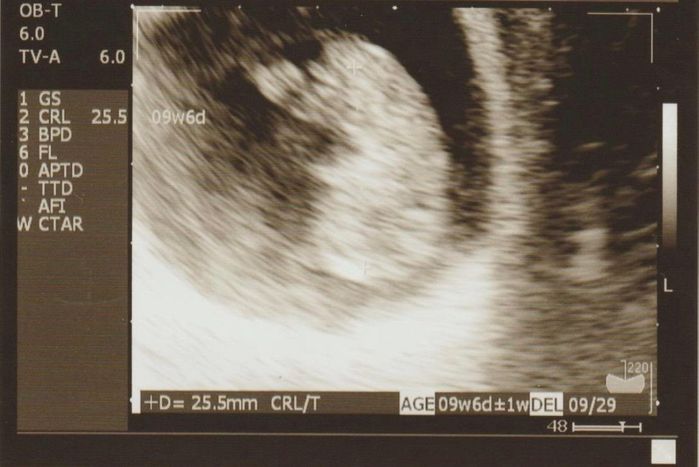

手足が確認できる - 妊娠9週目のエコー写真

D=25.5mm 手足が確認できる

初めてパパも一緒に病院へ行きました。画面にうつる我が子を見たパパは感動していました。手足が見えて、心臓も元気にパクパクと動いているのが確認でき一安心です。義母にもこの日のエコー写真を持って妊娠の報告に行きました。この頃、悪阻の一つなのか“ゲップ”がよく出るようになっていましたが、気持ち悪くて吐いてしまうようなことは一切なく、元気いっぱいのマタニティライフを楽しんでいました。